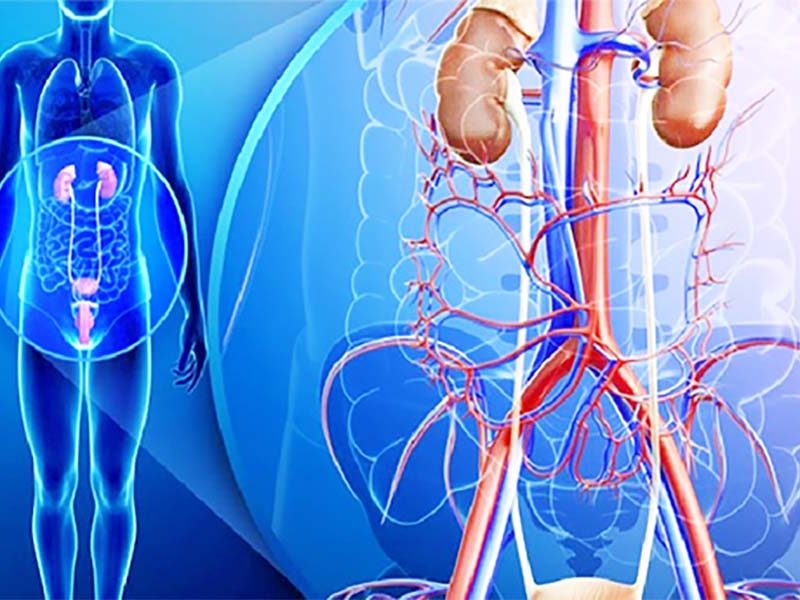

Nephrology & Urology

Our Nephrology and Urology services focus on the diagnosis and treatment of kidney and urinary tract disorders, with integrated support from critical care and dialysis services.